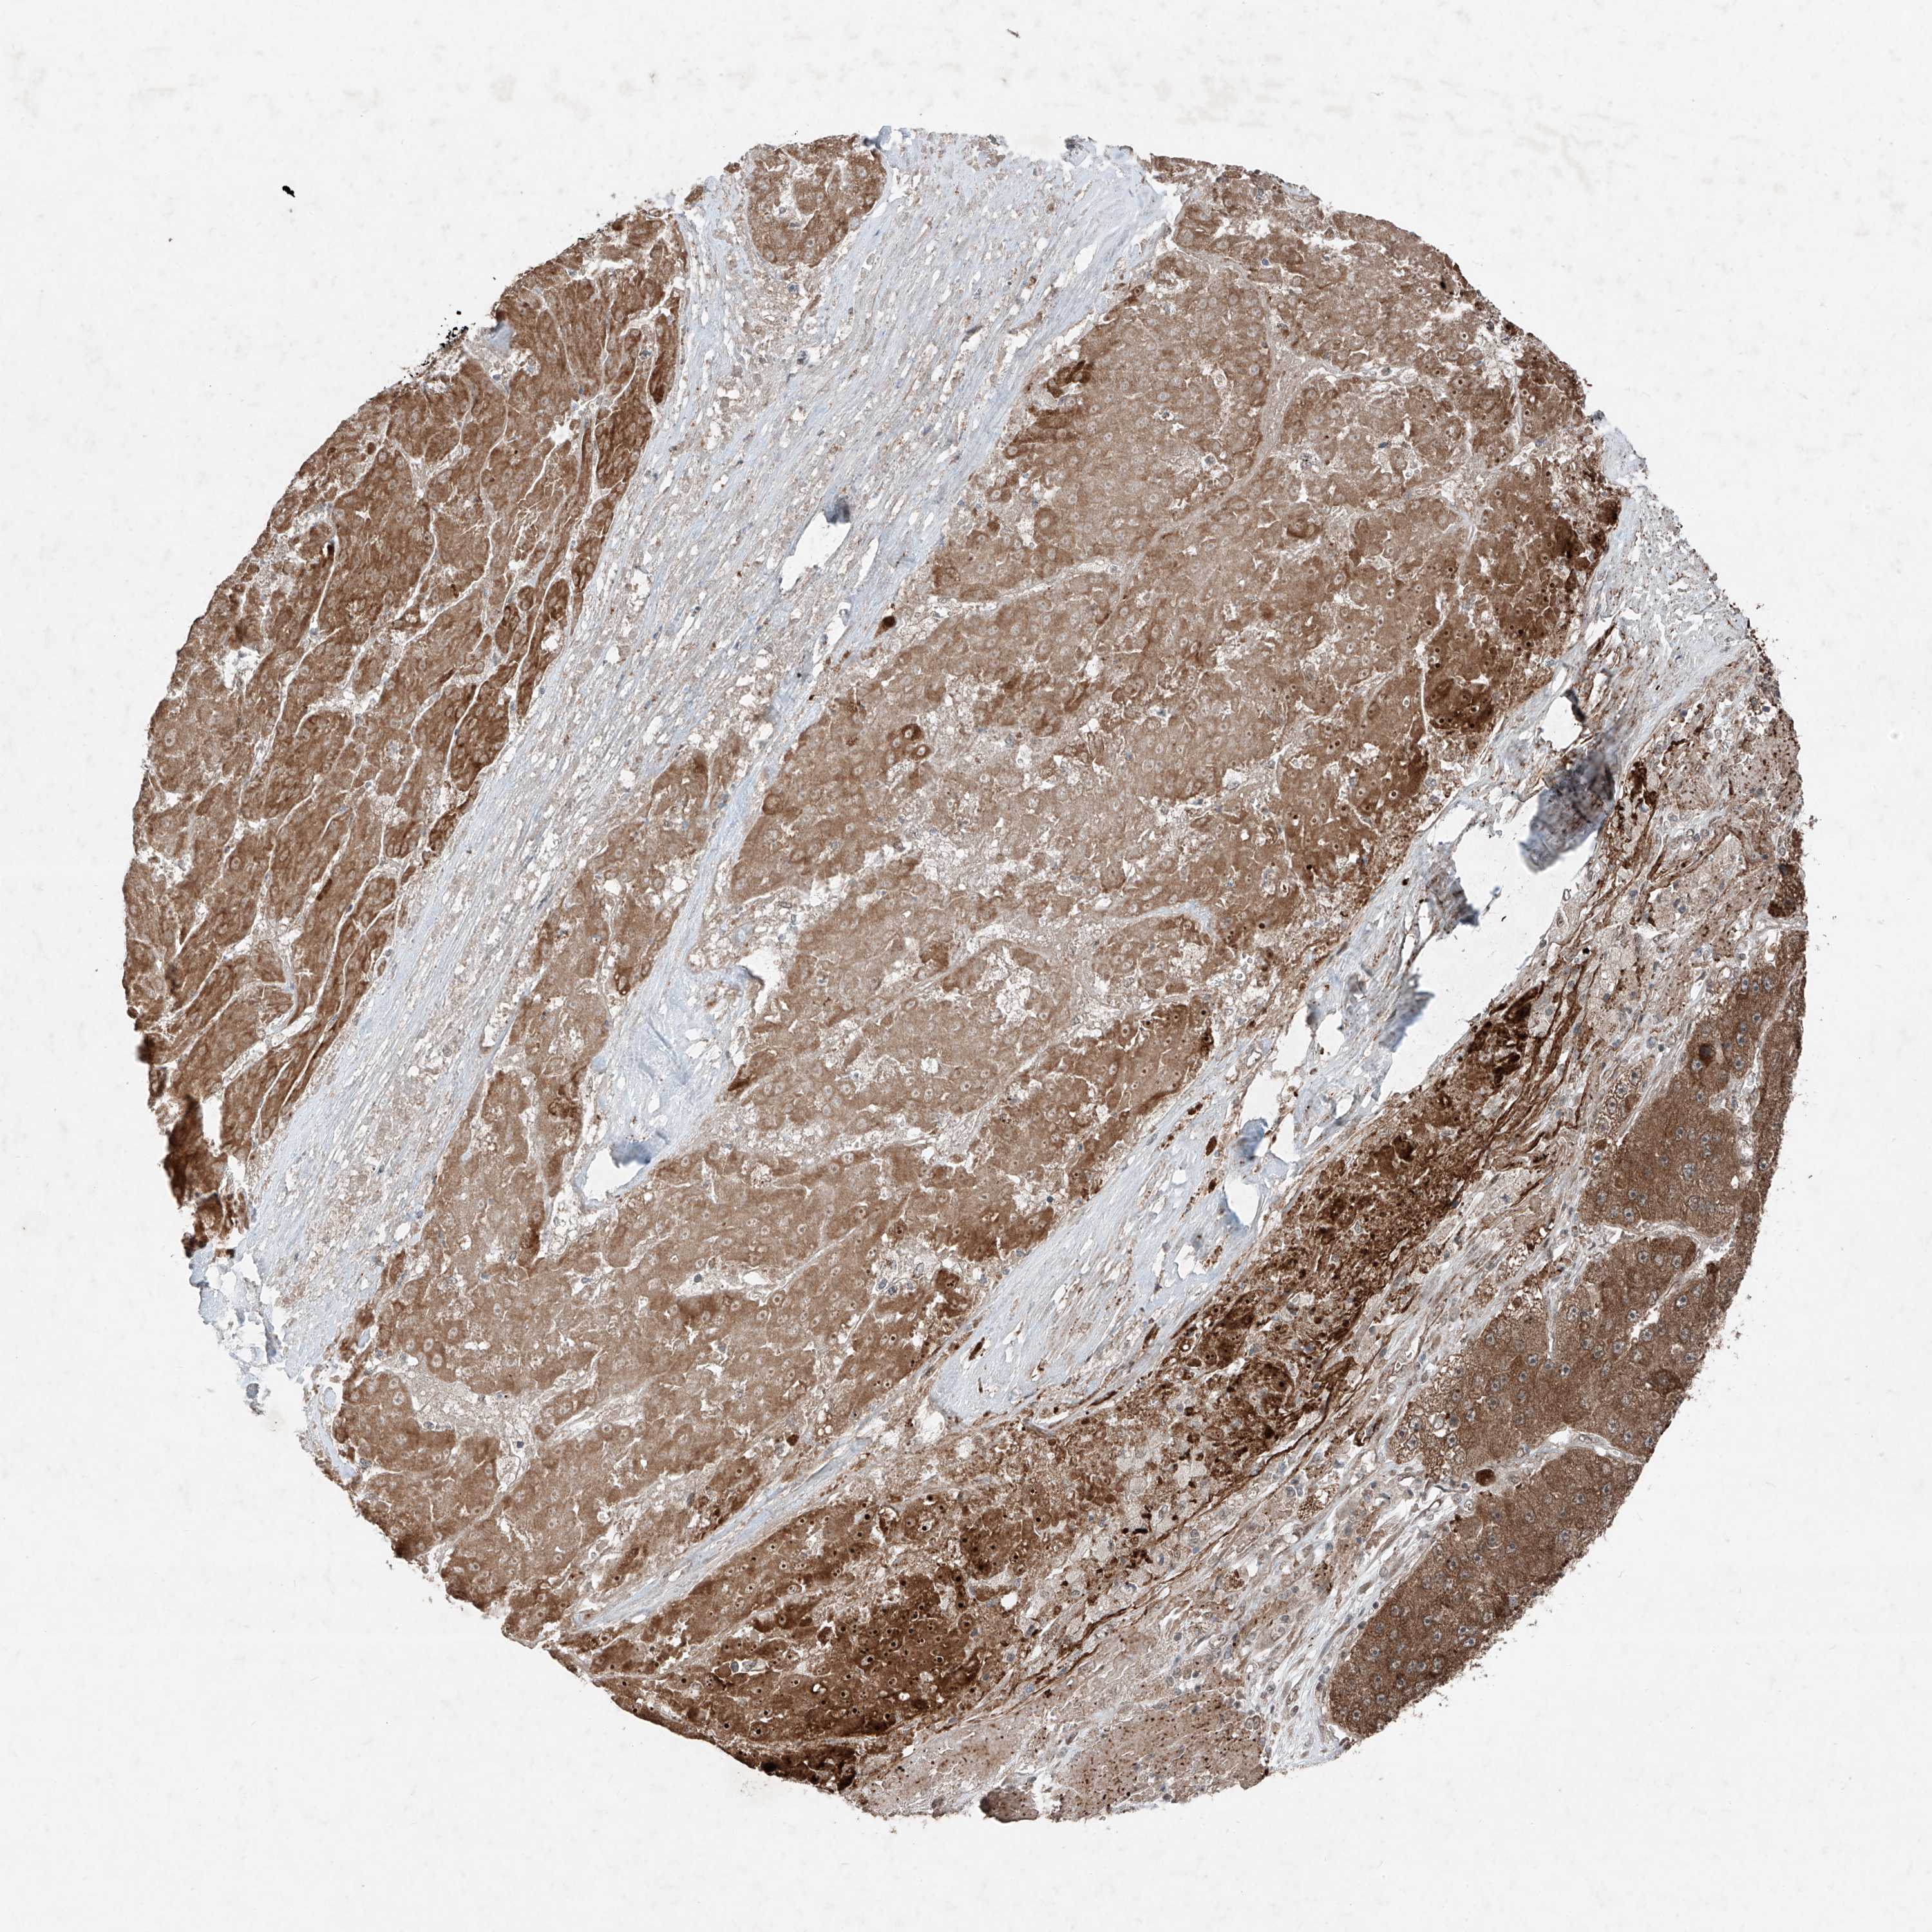

LIVER CANCER - Protein expressioni

A mouse-over function shows sample information and annotation data. Click on an image to view it in a full screen mode. Samples can be filtered based on level of antibody staining by selecting one or several of the following categories: high, medium, low and not detected. The assay and annotation is described here.

Note that samples used for immunohistochemistry by the Human Protein Atlas do not correspond to samples in the TCGA dataset.

Antibody stainingi

Antibody staining in the annotated cell types in the current human tissue is reported as not detected, low, medium, or high, based on conventional immunohistochemistry profiling in selected tissues. This score is based on the combination of the staining intensity and fraction of stained cells.

Each image is clickable and will lead to virtual microscopy that enables deeper exploration of all samples and also displays staining intensity scores, fraction scores and subcellular localization as well as patient and tissue information for each sample.

Antibody HPA031452

Staining

High

Medium

Low

Not detected

Intensity

Strong

Moderate

Weak

Negative

Quantity

>75%

75%-25%

<25%

None

Location

Nuclear

Cytoplasmic/membranous

Cytoplasmic/membranous,nuclear

Cholangiocarcinoma

Carcinoma, Hepatocellular, NOS